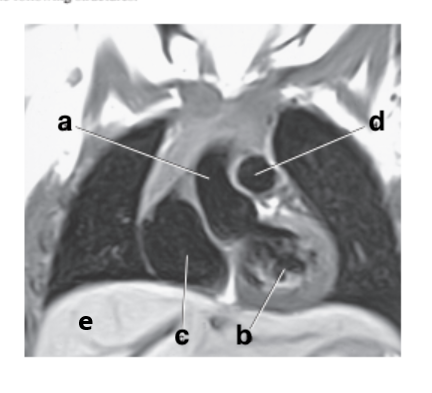

What is letter b ?

Esophagus

Which letter is the Descending aorta ?

f

Which letter is the ascending aorta ?

What is letter a ?

Ascending aorta

What is letter c ?

Hemiazygos vein

What is letter e ?

Aortic Arch

What is letter d ?

Pulmonary trunk

Which letter is the descending thoracic aorta ?

e

What is letter g ?

Descending aorta

Descending thoracic aorta

Trachea